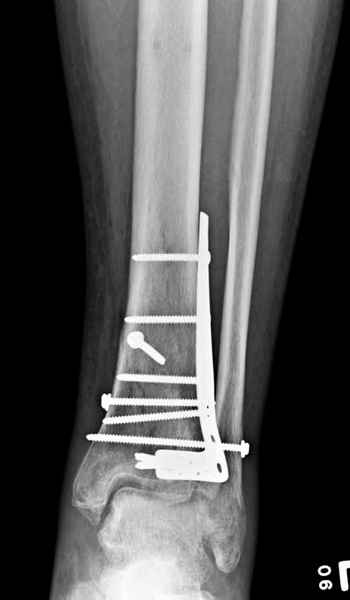

В приложении метафизарный перелом у ребёнка 14лет, с распространением линии перелома на зону роста.

Уважаемый коллега! Обычно, хирургичское лечение переломов пилона начинают с остеосинтеза малоберцовой кости (чего не продемонстрировали коллеги из Новокузнецка). В Вашем случае нет убедительных данных за перелом малоберцовой кости, так что, видимо, этот этап вы пропускаете. После чего переходят собственно к пилону - основные усилия в лечении которого необходимо направить на устранение импрессии (отчетливо видна на боковой R-грамме), затем пластика дефекта ну и накостный остеоинтез платиной, коих достаточно много. Хотел бы предостеречь Вас от: закрытой "малоинвазивной" техники в данном случае, так как для устранения импрессии малоинвазивно необходим определенный опыт и начинать с этого я бы не стал, использовать пластину Pilon Plate-имплант сложный в установке и , опять же, требует определенных навыков. Я бы синтезировал традиционной пластиной "лист клевера" с угловой стабильностью.

В примере показан не перелом пилона, а эпифизеолиз, м/берцовую кость сознательно не фиксировал(длина её восстановлена, ротации нет),у детей стараемся минимизировать операц.травму, несколько позже разрешил полную нагрузку на ногу(4 недели). Но принцип фиксации б/берцовой кости м.б. таким же.

Проблем с закрытой(прямой или непрямой) репозицией возникнуть не должно, даже при небольшом опыте, перелом как раз для этого, суставная поверхность и метафиз рассколоты, смещение небольшое. В крайнем случае можно сделать неболшой передний доступ для репозиции и остеосинтеза винтами сустава, а дальше обязательно малоинвазивно медиальную плату или аппарат.